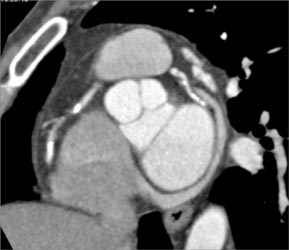

Patent Saphenous Bypass Grafts